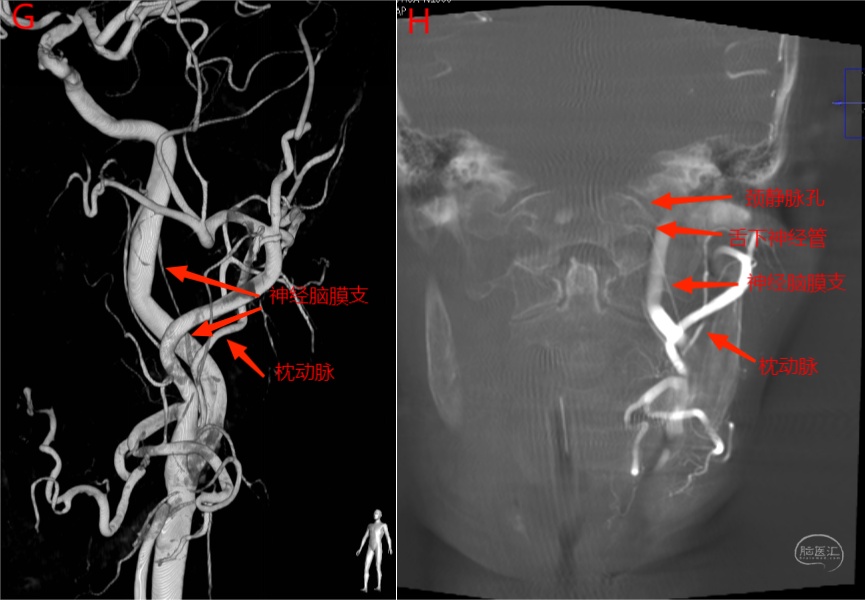

图15 左侧颈总动脉3D(G)及Xper CT(H)图像。可见咽升动脉神经脑膜支自枕动脉发出,向上走形进入舌下神经管。